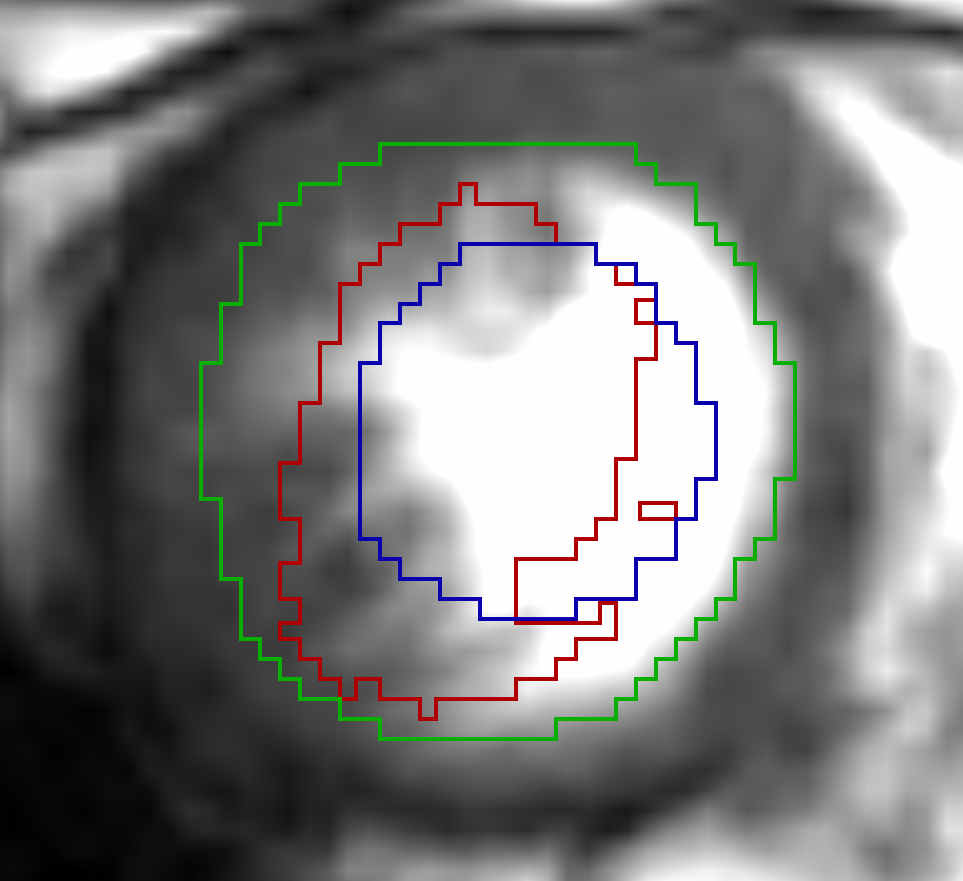

For the cardiac datasets the DVF for mapping the systolic phase to diastolic phase showed better results (DSC: 0.90, HD: 10.35 mm, ASSD: 1.49 mm) compared to the registration from diastolic to systolic phase (DSC: 0.81, HD: 13.12 mm, ASSD: 1.95 mm). We attribute this direction-dependent behaviour to the resampling of the Sunnybrook datasets. In the diastolic images the border of the LV segmentation is in the area of a high gradient in the deformation field where small and large deformations meet. Due to the nearest neighbour interpolation used for resampling the segmentation masks, the mask for interpolated slices is either too small or too large with respect to the linearly interpolated image slices. An example is shown in Fig. 3. However, to exclude an impact of the networks design we repeated the registration with switched input channels. The repeated experiments showed similar results and confirm the more accurate evaluation results from systolic to diastolic phase. Another point that contradicts a methodological failure is that for the lung datasets the better performance was distributed equally.

Refer to caption a) x,y-plane of SC-HYP-38 Refer to caption b) SC-HYP-38 along z-axis

Figure 3: In this figure the result for registering extreme systolic to diastolic phase for case SC-HYP-38 is depicted. The spikes in z-direction of the calculated contour (red) in b) and the closeness of the input contour (green) to tissue with a lower motion amplitude are an indicator that a reason for the poor registration result lies in the resampling along the z-axis and the nearest neighbour interpolation.